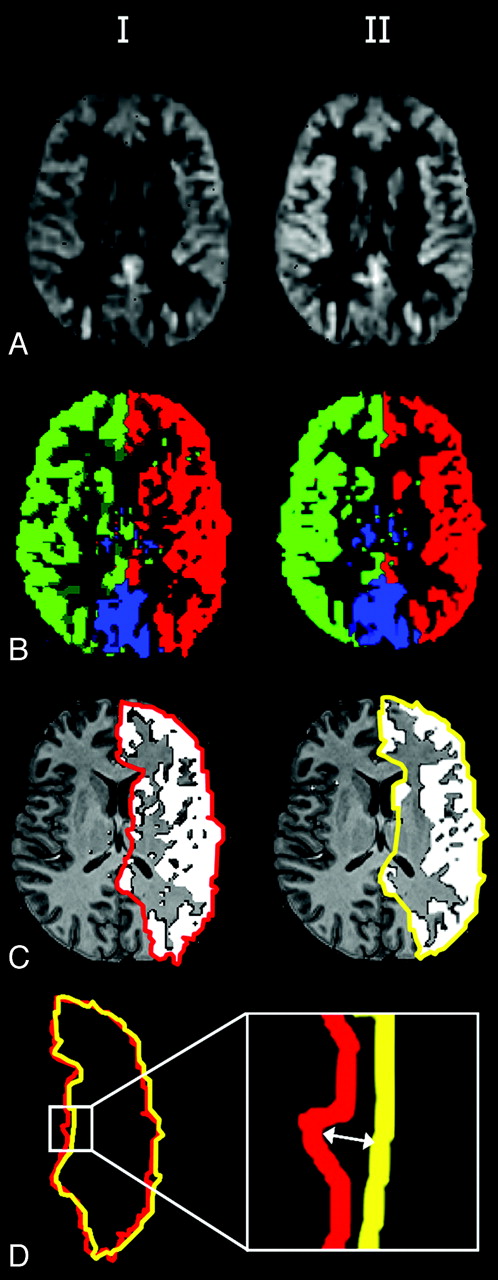

A and B, Sagittal and axial 3D T1-weighted images in which the imaging volume and labeling plane of planning-free selective ASL are illustrated. C, Labeling efficiency is spatially manipulated within the labeling plane.

Axial nonselective perfusion-weighted images (A) and flow territories (B) of 2 sessions, manual outlining (C) and the distance between flow-territory boundaries (D).

The nonselective perfusion-weighted image and flow territories of the ICAs and the BA obtained by planning-free selective ASL in a single subject are shown in Fig 2A, B. Intrasession repeated flow mapping yielded comparable flow territories for all controls (100%) and for 8 of 10 patients (80%). Figure 3 shows the flow territories based on the first and second halves of a selective ASL scan in an 80-year-old woman with a right ICA stenosis of 70%–99%. Intrasession repeated flow mapping yielded similar flow territories with enlargement of the contralateral left ICA flow territory, though some differences could be observed at the level of the basal ganglia. In 2 patients, gross motion artifacts led to uninterpretable flow-territory maps.